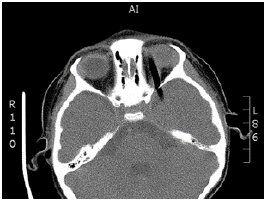

The tomography showed an intraorbital route of the foreign body towards the right side, and above the left eyeball towards the temporal lobe; no intraconal or intraocular lesions were evident, and no intracranial, subdural or epidural hematomas or retroconal bleeding were observed (Figures 1 and 2).

Intracranial trajectory of the foreign body.

Figure 2: Intracranial trajectory of the foreign body.

Source: Document obtained during the study.